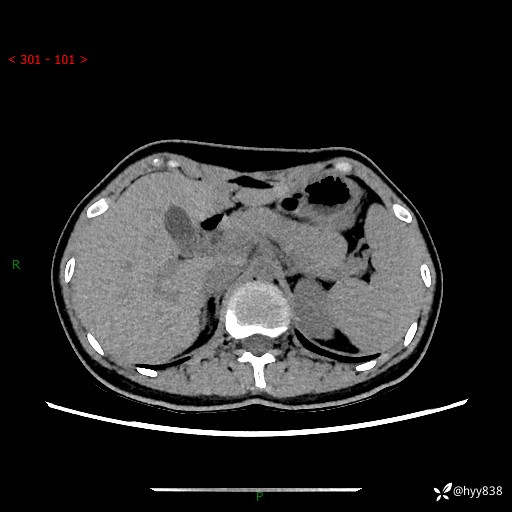

性别:女

年龄:23岁

简要病史:外院发现肝结节,来我院进一步增强确诊

上腹部CT平扫+增强